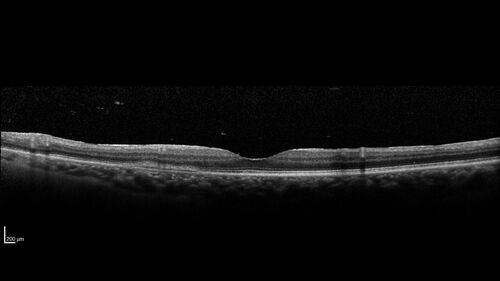

Birdshot Chorioretinitis - Chronic Untreated with Drusen Like Material in Macula

72 year old female with vision changes for years just now diagnosed with Birdshot.